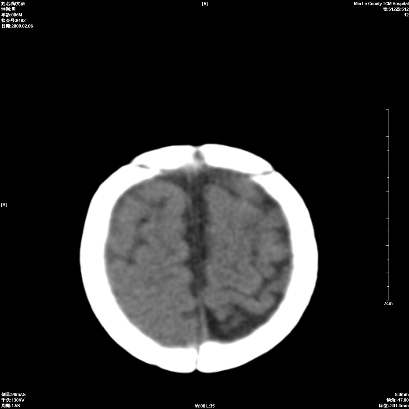

以下是引用wxq2008在2009-2-6 17:01:00的发言:[br]hie后遗症脑萎缩。

以下是引用学医在2009-2-6 21:45:00的发言:[br]hie后遗改变